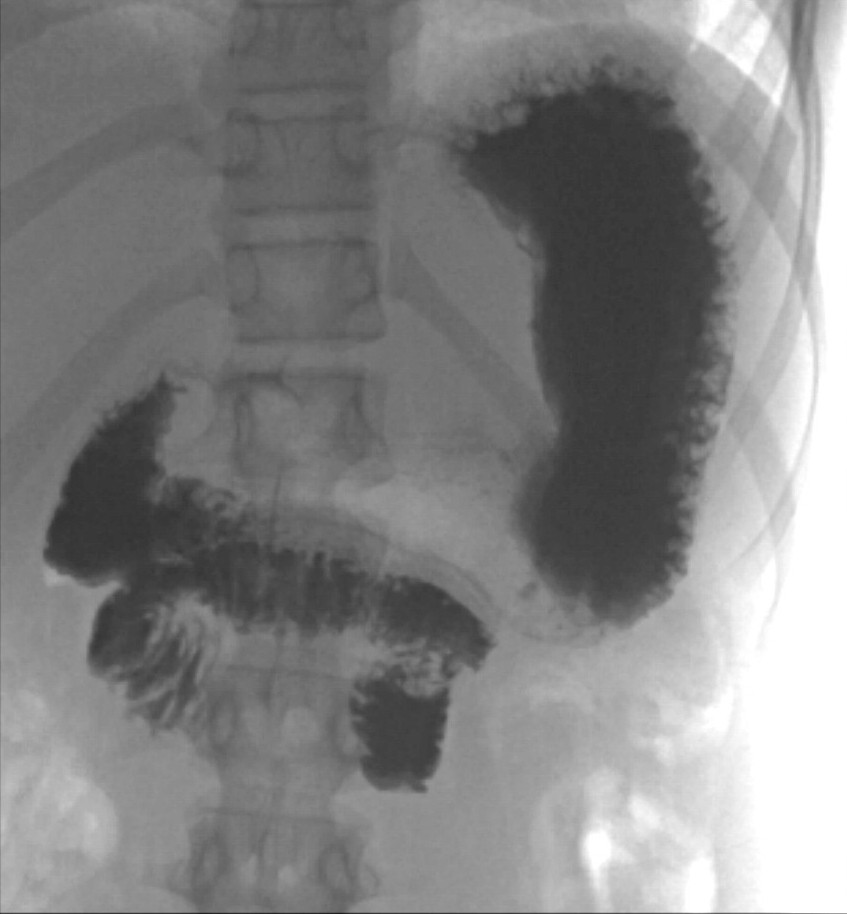

The girl was kept under observation throughout the weekend. Her general condition had improved, and she had little abdominal pain and no episodes of vomiting. Her electrolyte levels quickly normalised following initiation of fluid therapy. On Monday morning, an ultrasound examination was performed by an experienced paediatric radiologist who confirmed the whirl sign (Figures 1 and 2) and who suspected concomitant volvulus (where a loop of intestine twists about its own axis). The diagnosis was confirmed by an upper gastrointestinal series, which showed passage of contrast to the proximal small intestine, but no further (Figure 3). The transition between the duodenum and small intestine was just to the left of the midline, caudal to the level of the duodenal bulb, which suggested malrotation with volvulus. The explanation for the patient's long-term symptoms had finally been found (Figure 4).

Figure 3 Upper gastrointestinal series (x-ray of oesophagus, stomach and duodenum). Contrast can be seen in the stomach and…

Figure 3 Upper gastrointestinal series (x-ray of oesophagus, stomach and duodenum). Contrast can be seen in the stomach and scattered throughout the duodenum, which has a typical 'corkscrew' appearance, with absence of contrast filling in the jejunum. The duodenum also has atypical positioning; normally the duodenum is further up and to the left of the midline than seen here.

When volvulus is present, an upper gastrointestinal series will show an obstruction, often with a 'corkscrew' appearance of the duodenum and a lack of contrast filling beyond this point. Water-soluble contrast should be used for x-rays when volvulus is suspected, as bowel resection may be required with the associated risk of intraoperative contrast extravasation.